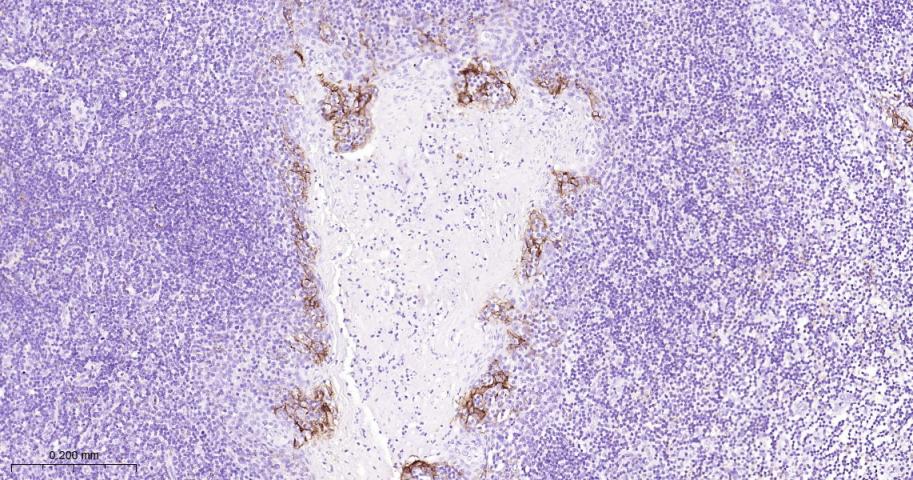

Paraformaldehyde-fixed, paraffin embedded Human Chronic tonsillitis; Antigen retrieval by boiling in sodium citrate buffer (pH6.0) for 15 min; Antibody incubation with PD-L1 Monoclonal Antibody, Unconjugated(bsm-43073R) at 1:200 overnight at 4°C, followed by conjugation to the bs-0295G-HRP and DAB (C-0010) staining.

Paraformaldehyde-fixed, paraffin embedded Human Tonsil; Antigen retrieval by boiling in sodium citrate buffer (pH6.0) for 15 min; Antibody incubation with PD-L1 Monoclonal Antibody, Unconjugated(bsm-43073R) at 1:200 overnight at 4°C, followed by conjugation to the bs-0295G-HRP and DAB (C-0010) staining.